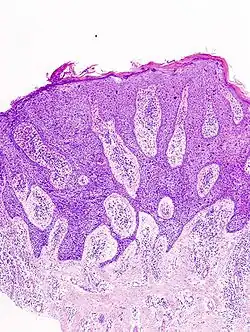

Histological characteristics

Histopathologically, the epidermis in cSCC in situ (Bowen's disease) will show hyperkeratosis and parakeratosis. There will also be marked acanthosis with elongation and thickening of the rete ridges. These changes will overly keratinocytic cells, which are often highly atypical and may have a more unusual appearance than invasive cSCC. The atypia spans the full thickness of the epidermis, with the keratinocytes demonstrating intense mitotic activity, pleomorphism, and greatly enlarged nuclei. They will also show a loss of maturity and polarity, giving the epidermis a disordered or "windblown" appearance.

Two types of multinucleated cells may be seen: the first will present as a multinucleated giant cell, and the second will appear as a dyskeratotic cell engulfed in the cytoplasm of a keratinocyte. Occasionally, cells of the upper epidermis will undergo vacuolization, demonstrating an abundant and strongly eosinophilic cytoplasm. There may be a mild to moderate lymphohistiocytic infiltrate detected in the upper dermis.[12]